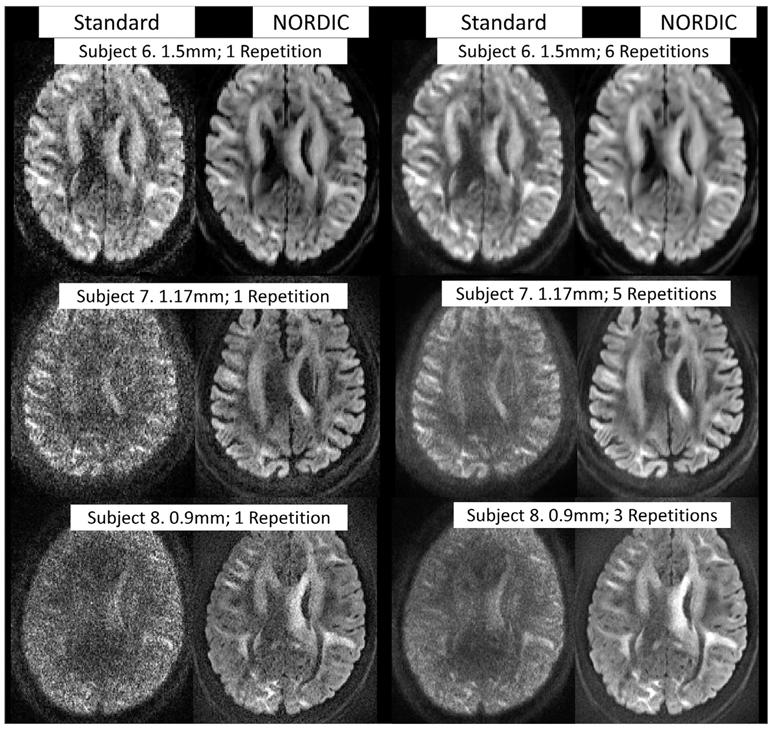

Diffusion-weighted magnetic resonance imaging (dMRI) has found great utility for a wide range of neuroscientific and clinical applications. However, high-resolution dMRI, which is required for improved delineation of fine brain structures and connectomics, is hampered by its low signal-to-noise ratio (SNR). Since dMRI relies on the acquisition of multiple different diffusion weighted images of the same anatomy, it is well-suited for denoising methods that utilize correlations across the image series to improve the apparent SNR and the subsequent data analysis. In this work, we introduce and quantitatively evaluate a comprehensive framework, NOise Reduction with DIstribution Corrected (NORDIC) PCA method for processing dMRI. NORDIC uses low-rank modeling of g-factor-corrected complex dMRI reconstruction and non-asymptotic random matrix distributions to remove signal components which cannot be distinguished from thermal noise. The utility of the proposed framework for denoising dMRI is demonstrated on both simulations and experimental data obtained at 3 Tesla with different resolutions using human connectome project style acquisitions. The proposed framework leads to substantially enhanced quantitative performance for estimating diffusion tractography related measures and for resolving crossing fibers as compared to a conventional/state-of-the-art dMRI denoising method.

扩散加权磁共振成像(dMRI)在神经科学和临床应用的广泛领域中具有重要的应用价值。然而,为了提高精细脑结构和连接组学的描绘能力,需要高分辨率的 dMRI,但这受到其信噪比(SNR)低的限制。由于 dMRI 依赖于对同一解剖结构的多个不同扩散加权图像的采集,因此非常适合利用图像序列之间的相关性来提高表观 SNR 并随后进行数据分析的去噪方法。在这项工作中,我们引入并定量评估了一种全面的框架,即用于处理 dMRI 的基于分布校正的噪声减少(NORDIC)PCA 方法。NORDIC 使用 g 因子校正的复 dMRI 重建的低秩建模和非渐近随机矩阵分布来去除无法与热噪声区分开来的信号分量。在所提出的框架的实用性上,通过使用人类连接组项目风格采集在 3 Tesla 上获得的不同分辨率的模拟和实验数据进行了证明。与传统/最先进的 dMRI 去噪方法相比,所提出的框架可显著提高估计扩散轨迹相关测量值和解决交叉纤维的定量性能。